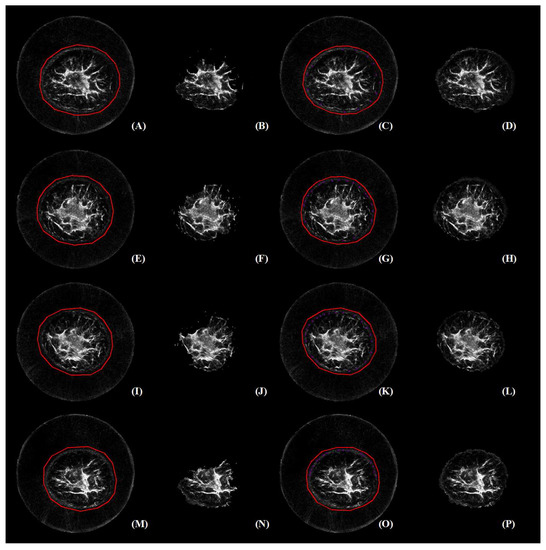

3.2. Perceived Evaluation

3.3. Quantitative Comparison